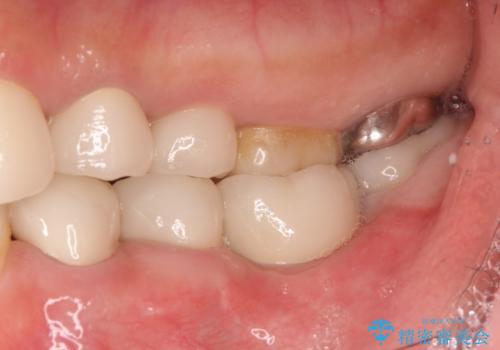

[重度の骨吸収] 顎骨の再建を伴うインプラント治療

![[重度の骨吸収] 顎骨の再建を伴うインプラント治療の症例 治療後](https://seimitsushinbi.jp/wp/wp-content/uploads/2019/05/41890b7a4fba7bded1b9c70039ff5e75-500x350.jpg)